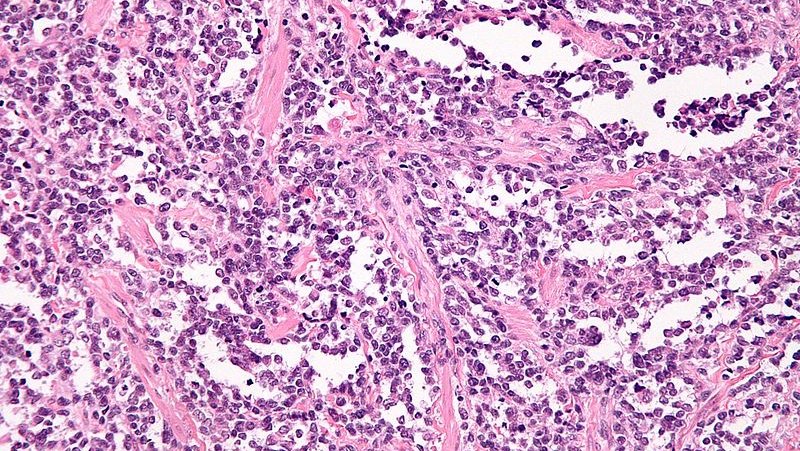

Soft Tissues: Alveolar Rhabdomyosarcoma

(A) Histological Appearance Of Alveolar Rhabdomyosarcoma: Fibrous

alveolar rhabdomyosarcoma fibrous histological connective septa forming

(A) Histological Appearance Of Alveolar Rhabdomyosarcoma: Fibrous

alveolar rhabdomyosarcoma histological fibrous septa connective figure forming findings implications prognostic pseudo

Alveolar Rhabdomyosarcoma | Ottawa Atlas Of Pathology

Alveolar Rhabdomyosarcoma; A. Typical Architecture With Pseudoalveolar